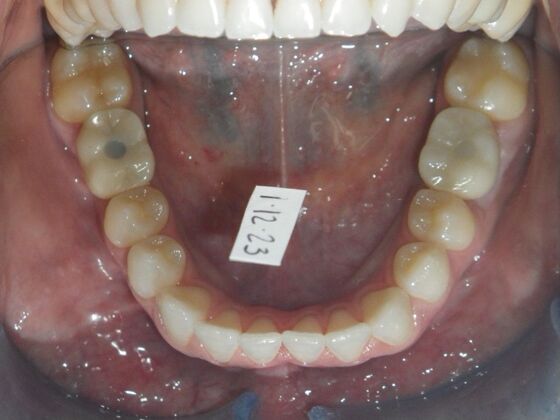

Invisalign: Case 17

This patient was an awesome dental assistant for our practice and we were all very sad when she had to move closer to her home. She was very interested in correcting some minor spacing and rotations in her upper and lower anterior teeth and to decrease her overbite as well.Treatment took about 12 months, but we were pleased with the results and fabricated clear invisalign vivera retainers. We are still hoping one day she will return to be with us again.